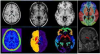

MARS (Multi-Atlas Robust Segmentation)

Specifically, this software has integrated several state-of-the-art multi-atlas based segmentation methods, such as majority voting, local weighted voting, and non-local patch based segmentation methods.

More importantly, we also included our recently-developed joint sparse patch based segmentation method in this software. Compared with convention methods, our method has the following advantages: (1) add sparsity constraint to suppress the influence of misleading patches; (2) reduce the joint risk of two patches jointly making the same segmentation errors, and (3) use iterative framework to correct the possible mis-segmentations.